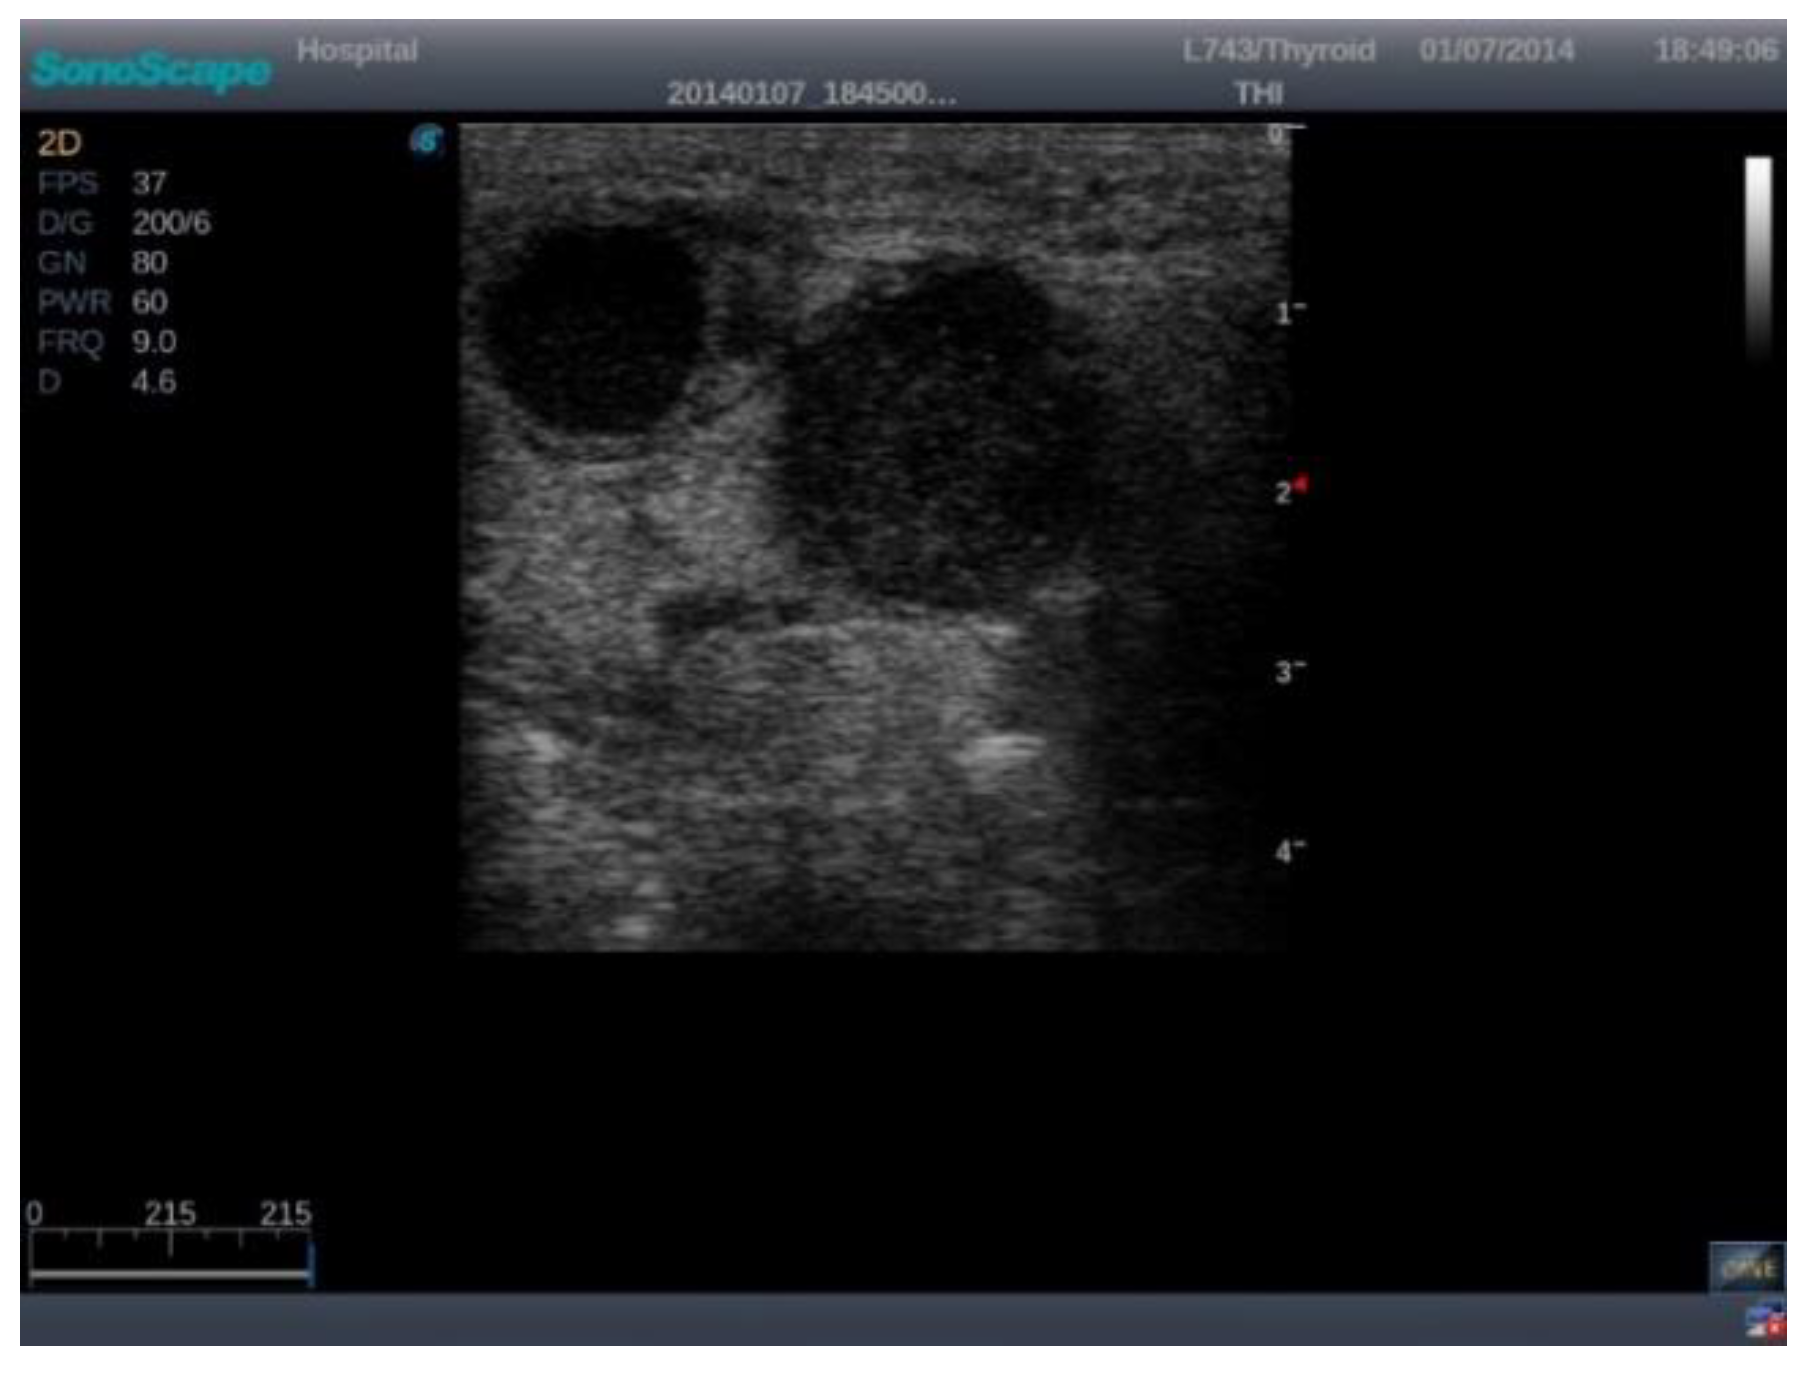

The images were exported from the device used in .jpg format (Figure 1) directly from the US machine and processed by cropping them and resizing them to 469 × 469 pixels (Figure 2).

Figure 1. Raw US machine image of a malignant lymph node.

Jmms 12 00029 g001